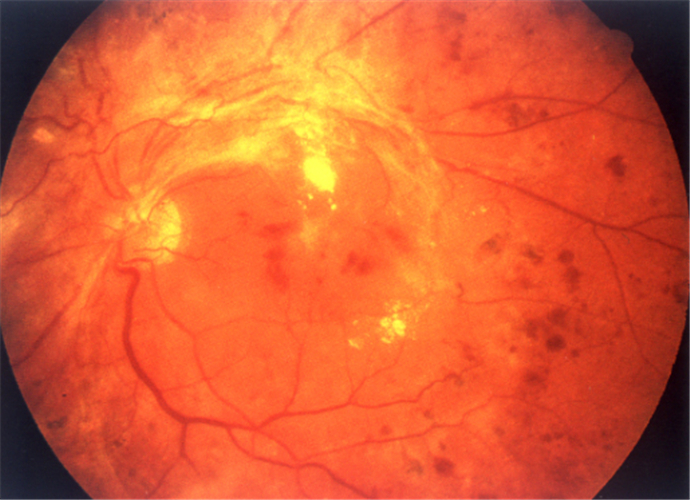

糖尿病人視網膜脫落